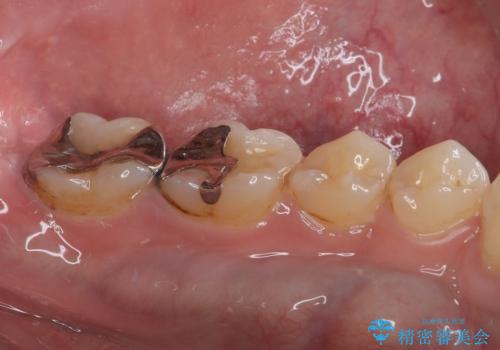

銀歯を白くしたい セラミックインレー修復

- 当院に矯正治療で通院されており矯正治療後に銀歯が目立つので白くしたいとのことでした。

拡大鏡視野下でメタルインレー、虫歯の除去を行い、セラミックインレーに適した形に整えました。